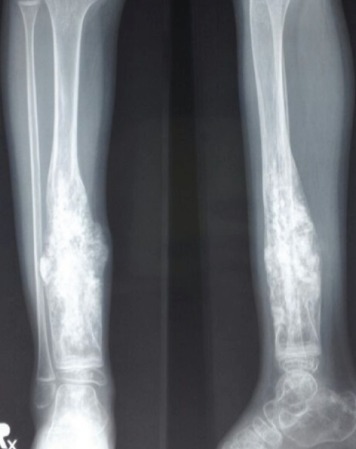

Limb preservation (salvage) surgery aims to remove malignant bone or soft tissue tumors while preserving the limb’s function and appearance, avoiding amputation in over 90% of cases today. Performed after neoadjuvant chemotherapy, it involves wide tumor resection with clear margins, followed by reconstruction.